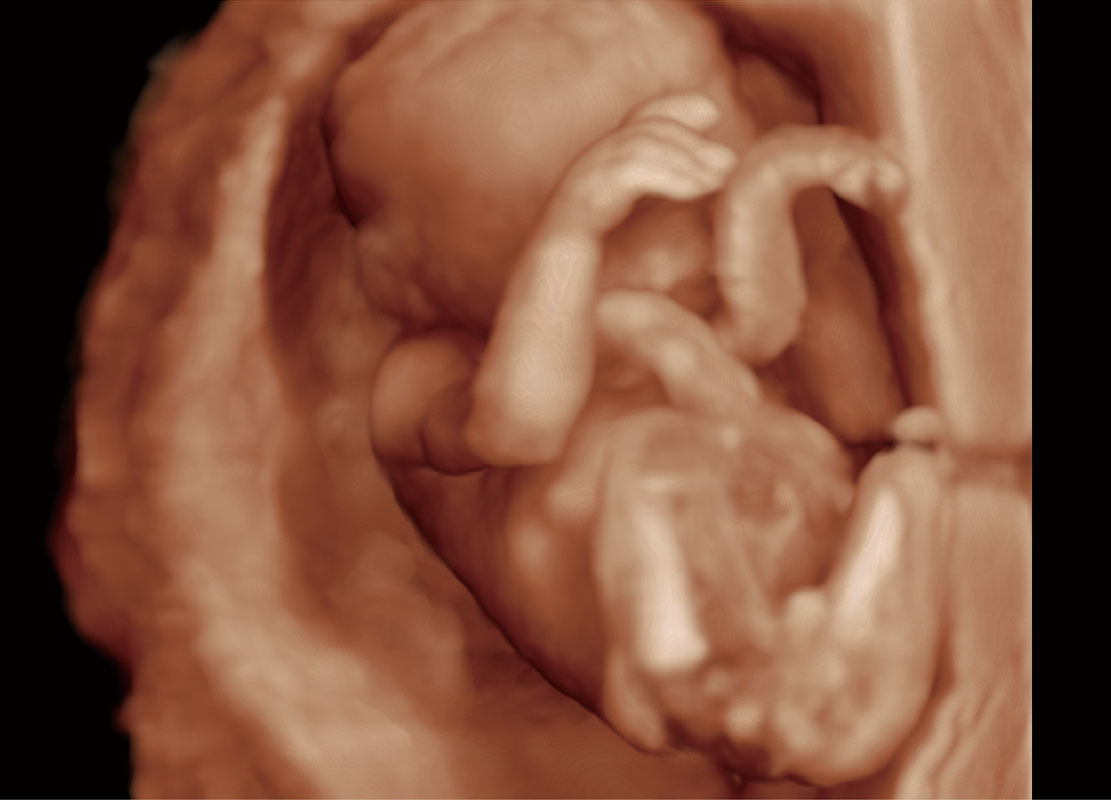

高分辨率容积成像-早孕胎儿

胎儿体循环